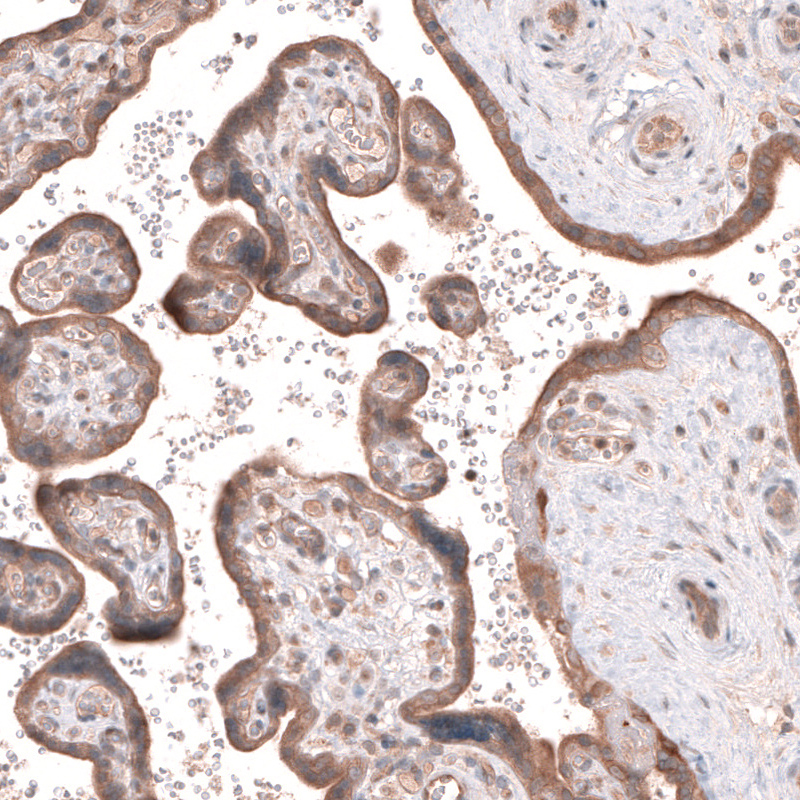

Immunohistochemical staining of human prostate shows moderate cytoplasmic positivity in glandular cells.